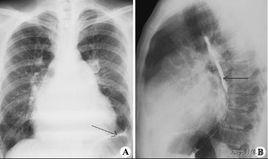

Kerley B線: 是由於肺間質水腫引起小葉間隔增寬,在兩肺下葉外側可形成水平線狀影,常位於肋膈角區,為長約1-3厘米、寬約1-2毫米的水平橫線,一般垂直於側肋胸膜(位於肋膈角上方與胸壁或膈肌垂直的條狀影子) ,是肺小葉間隔內積液的表現,是慢性肺淤血的特徵性表現。

克利線(Kerley lines)是胸部影像學下的一種影像學徵象,一般出現於間質性肺水腫患者。